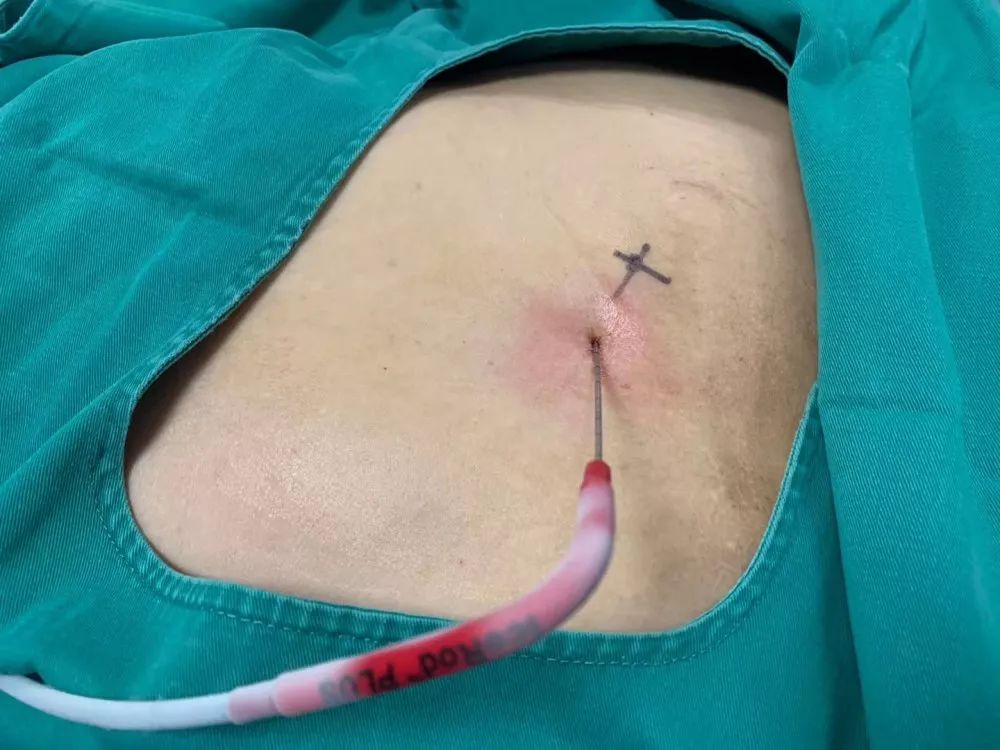

2017年9月29日,从CT影像看到右肾情况更为严重。为减缓肿瘤增长的速度,专家进行商议后,最终决定由牛立志教授主刀为安图叔叔进行了右肾肿瘤冷冻消融术。手术开始后,牛立志教授在CT和超声引导下,同时使用两根冷冻针固定病灶,精准灭活肿瘤;术后很成功无不良反应。术后一周进行第二次双肾肿瘤冷冻消融术。安图叔叔儿子笑道:“当时真的很紧张,医生劝慰我无须担心,都交给他们,我们都很清楚知道父亲的病情,真的很感谢也很庆幸我父亲遇到复大的医护人员,免受开刀之痛。住院期间医护人员很尽心尽力的照顾父亲,手术的成功离不开他们的辛劳付出。”

冷冻治疗手术中